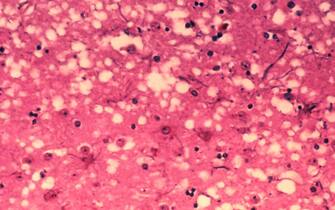

Secondo l'Iss, quello della "Mucca Pazza" è un agente infettivo virale, tuttavia il morbo conosciuto come "Bovine Spongiform Encephalopathy" è una delle malattie più temute degli ultimi decenni

9/23 ©Getty Images

La BSE è stata diagnosticata per la prima volta nel Regno Unito nel 1986. Si riteneva fosse una malattia specifica della specie bovina

Per anni è stato diffusissimo il timore di contrarre questa malattia comunque letale, al pari della rabbia, per esempio